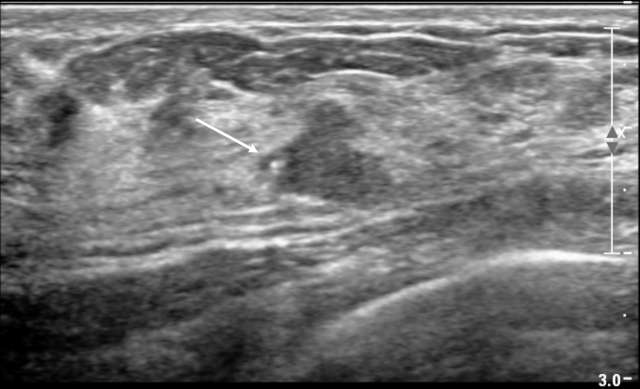

Outside of a mass, calcifications are generally harder to visualize as they may blend in with the hyperechoic speckles in the breast and Cooper ligaments. However, when an abnormal nonmass sonographic finding is identified (defined as a “discrete identifiable area of altered echotexture compared with that of the surrounding breast tissue that does not conform to a mass shape”) and demonstrates associated calcifications, such findings are frequently associated with malignancy3. Studies have shown that calcifications are present in up to 51% of malignant nonmass findings compared to 0-10% in benign nonmass findings3.